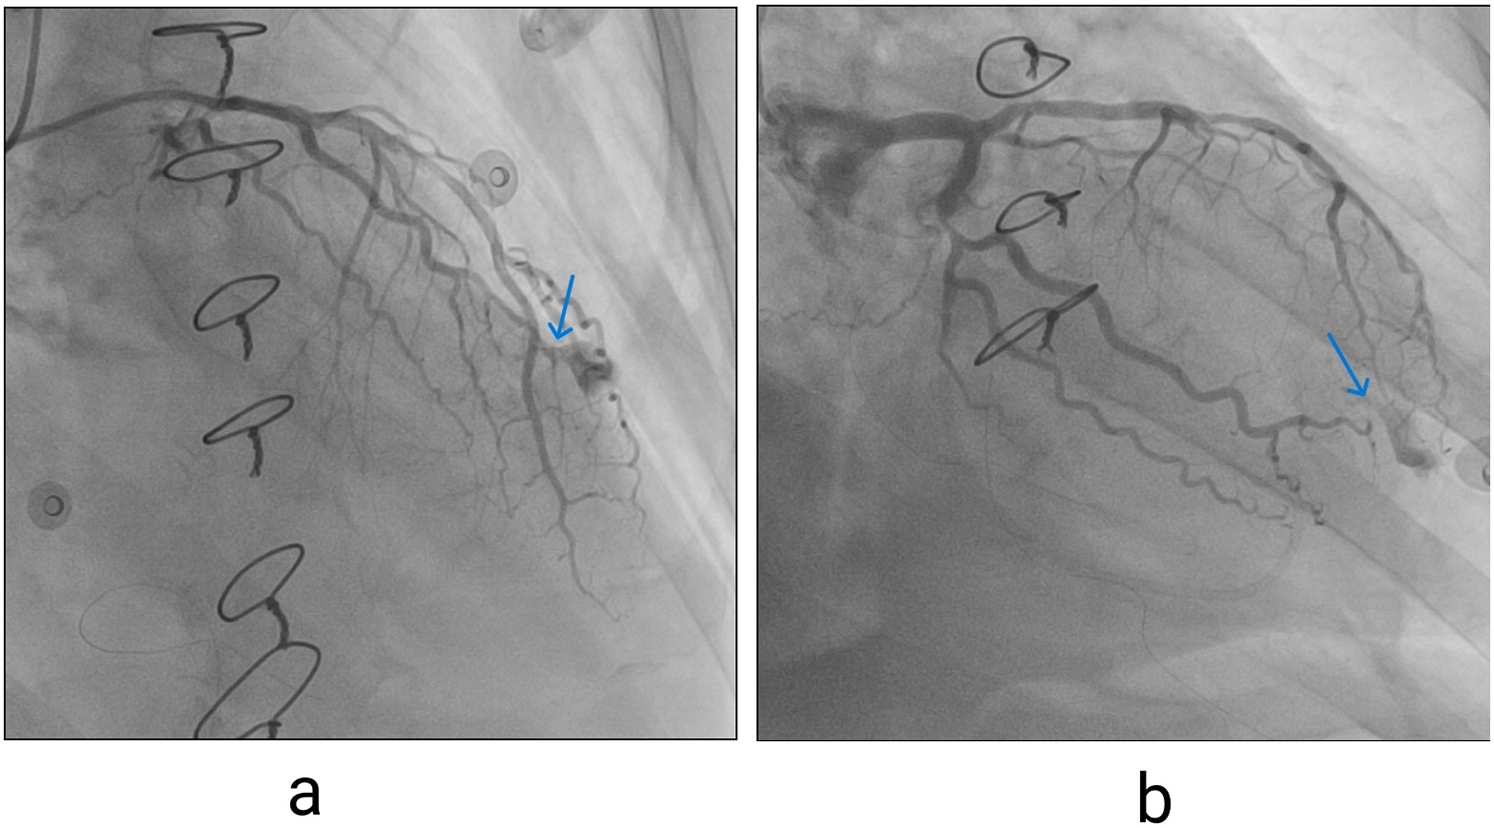

The patient was rushed to the cath lab, where invasive coronary angiography was performed. Significant stenosis of the Cx was noted, and extravasation of contrast from the distal segment of OM1 was identified. (Figures 3a,b).

Figure 3

(a) Contrast extravasation seen on invasive coronary angiography, left coronary artery in right anterior oblique (RAO) cranial view, blue arrow pointing to extravasation site. (b) Left coronary artery in RAO caudal projections (blue arrow pointing to extravasation site).